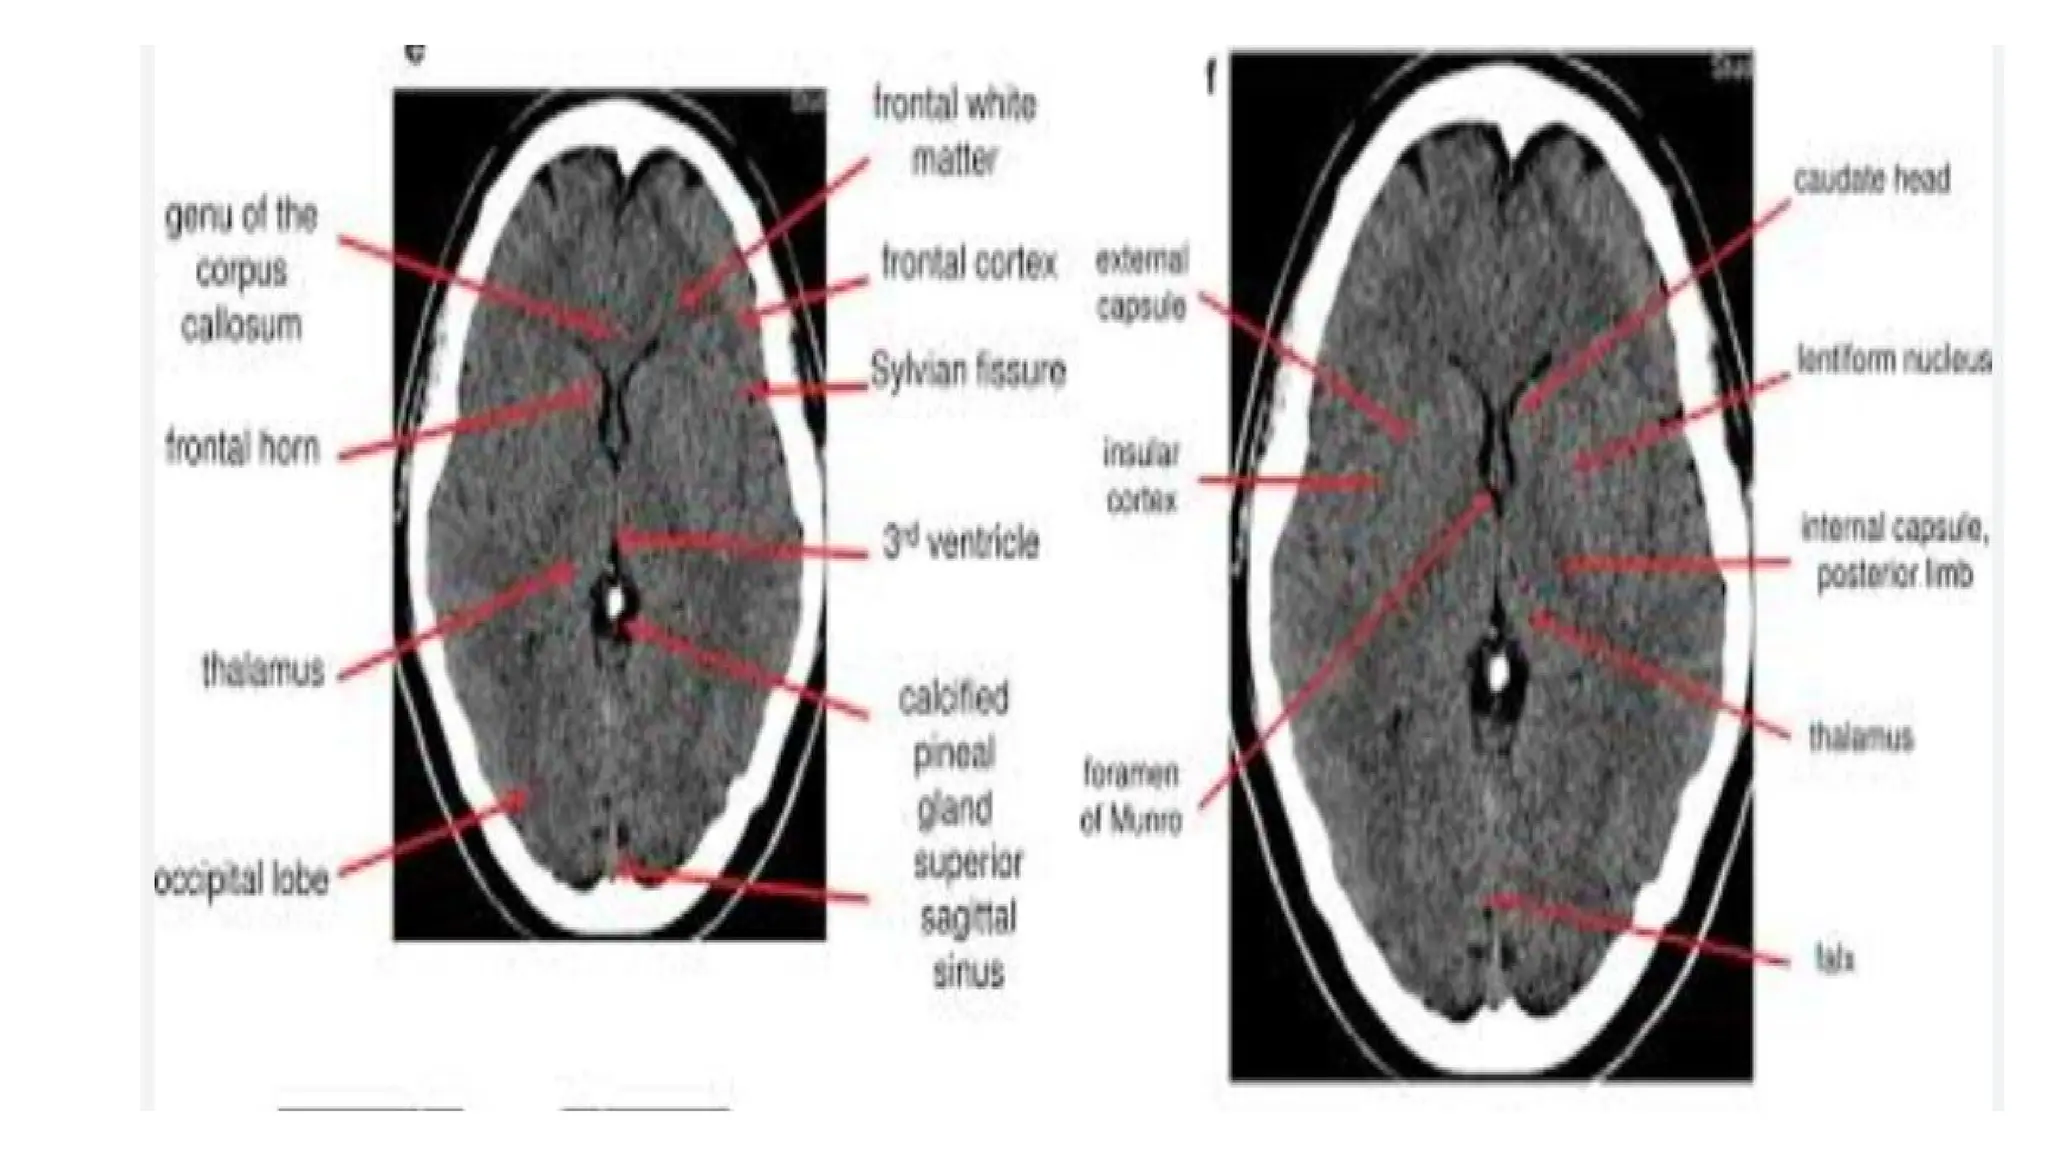

CT SCAN OF BRAIN:

• An imaging technique of the brain that reveal tumors, blood clots,

hemorrhages, or other abnormal anatomy.

• A series of computerized images of the brain at various levels are

taken to reveal normal anatomy or any abnormality.

• Routine scans of the brain usually begin at the base of the skull and

continue superiorly.

• Symmetry - Compare left and right side of the Midline

• Look for midline shift of cranium

• Cross-sectional anatomy - Review anatomical landmark for each

section.

• Brain tissue: gray matter, white matter, intracerebral lesions

• CSF space : ventricle (dilated or not)

• Skull and soft tissue: scalp swelling, fractures, sinuses, orbit

• Subdural windows: Look for blood collection adjacent to the skull

• Bone windows: Skull, orbit and sinuses, intracranial air

Normal scan:

• Ventricles are normal sized, the

grey versus white distinction is

clear.

• Midline is straight.

• Sulci are symmetrical on both sides.

• Skull is intact with no scalp edema.